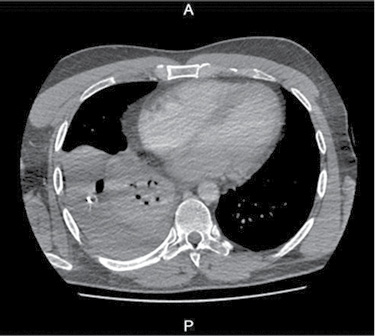

36 m. vyras P. D. atvyko į Gastroenterologijos skyrių patikslinti diagnozės planine kepenų biopsija. Praėjus 8 val. po procedūros, pacientas pajuto maudimą po dešiniuoju šonkaulių lanku punkcijos vietoje. Apžiūros metu pacientas buvo hemodinamiškai stabilus. Atlikus laboratorinius tyrimus, nustatyta saiki anemizacija (hemoglobinas – 128 g/l; norma – 135–160 g/l). Įtariant kraujavimą pilvaplėvėje, atlikta pilvo echoskopija: pilvo ertmėje laisvo skysčio nematyti, dešinėje pleuroje iki 4 cm laisvo skysčio ruožas. Konsultuota krūtinės chirurgo. Rekomenduota atlikti krūtinės ląstos rentgenogramą (Ro). Nustatytas beveik neoringas dešinysis plautis, pastebėta hidrotorakso požymių (1 pav.). Įtarus jatrogeninį hemotoraksą, krūtinės chirurgas atliko diagnostinę pleuros punkciją. Patvirtinus hemotorakso diagnozę, drenuota dešinė pleuros ertmė, išsiskyrė 400 ml kraujo. Tuo metu aktyvaus kraujavimo nenustatyta, hemodinamika išliko stabili, kartotiniuose laboratoriniuose tyrimuose – saiki anemizacija (hemoglobinas – 120 g/l). Atlikus kontrolinę rentgenogramą, nustatytas sumažėjęs skysčio kiekis pleuroje, buvo matyti kompresinių dešiniojo plaučio pakitimų. Įtariant sukrešėjusį hemotoraksą, atlikta skubi krūtinės ląstos KT (2 pav.), kuri patvirtino įtariamą patologiją. Tolesniam operaciniam gydymui pacientas perkeltas į Krūtinės chirurgijos skyrių. Atlikta skubi VATS (angl. video assisted thoracoscopic surgery). Operacijos metu pašalinta 1 000 ml krešulių, aktyvaus kraujavimo nenustatyta, diafragmos kupole rasta nedidelė hematoma. Pooperacinis periodas sklandus (3 pav.). Po trijų dienų geros būklės pacientas išleistas į namus.

2 pav. Krūtinės ląstos KT atlikus pleuros ertmės drenavimą (prieš operaciją)